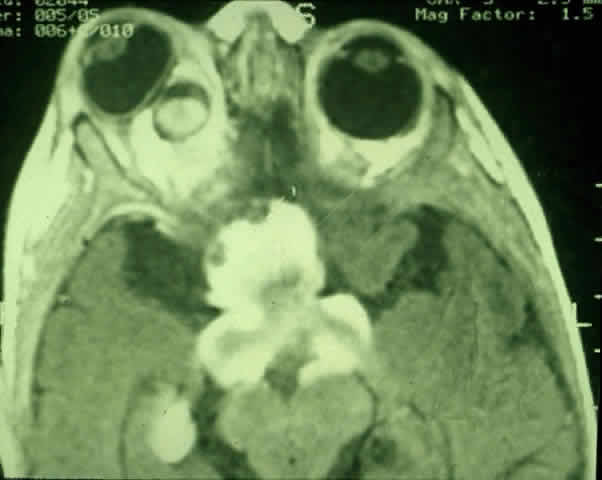

| Plain-film orbital X-ray may reveal concentric enlargement of the optic

foramen with preservation of a well-corticated margin due to a slow growth

of the tumor.4 A criterion for abnormality in one study that did not include any false-positives

in children is an optic foramen of 7 mm diameter, or 6.5 mm

and at least 1 mm larger than the contralateral foramen.67 Enlargement of the optic canal does not necessarily imply intracranial

extension of the glioma, because dural thickening and arachnoid hyperplasia

may cause such changes.68,69 In the series of Chutorian and colleagues, foramen enlargement was present

in 83% of patients with involvement of one optic nerve and in 67% of

those with chiasmal involvement.29 The pressure of the glioma on the anterior clinoid process and lateral

chiasmatic groove may produce a fossa with continuity of the optic canal, creating

a J-, pear-, or gourd-shaped sella turcica.70 Tumors that less commonly produce a similar flattening include trans-canalicular

extension of intraorbital neurofibromas, perioptic extension

of a craniopharyngioma, or pituitary adenoma.4 With the availability of computerized tomography (CT) and magnetic resonance imaging (MRI), invasive diagnostic techniques such as arteriography and pneumoencephalography should not be performed in the routine workup of presumed optic gliomas.71 CT scanning may demonstrate enlargement of the optic nerve or chiasm by a glioma (Fig. 3). Because optic gliomas typically appear isodense to normal brain,72 and because the degree of contrast enhancement ranges from imperceptible to moderate on CT imaging,73 the margins of the tumor may not be well delineated. Optic gliomas usually have a well-outlined fusiform shape, which may include kinking or buckling of the optic nerve. Chiasmal tumor appearance may range from a tubular thickening of both optic nerves and chiasm to massive, multilobular growths.74 Cystic spaces representing mucinous accumulation have been described. These cysts may enlarge and damage adjacent structures, requiring surgical intervention.74,75 Calcific change has also been documented in gliomas, but it is a rare radiologic finding.13 In following patients clinically, it is important to understand that radiologic progression of optic gliomas on CT scans may not correlate clinically with worsening visual function. Conversely, a decline or improvement in visual status may occur despite a lack of corresponding changes on neuroimaging.73,76 MRI has replaced CT scanning as the optimum test for imaging optic gliomas (Fig. 4 A and B). Optic gliomas have normal to slightly prolonged T1 relaxation times and appear isointense to slightly hypointense to normal brain on T1. Because many of these tumors have prolonged T2 relaxation times, images that are T2 weighted may be used to assess gross tumor margins and posterior extension.72 Optic nerve gliomas often demonstrate minimal enhancement after administration of contrast. To improve MR imaging of optic nerve lesions, a gadopentetate dimeglumine enhancement technique combined with fat suppression can be utilized. Unlike meningiomas, the thickened sheath from arachnoid hyperplasia associated with gliomas will not enhance.77 Although imaging should initially be performed in the axial plane to allow visualization of both the optic nerve and the posterior optic pathways, sagittal views are helpful in demonstrating chiasmal involvement; coronal views can be utilized to delineate intracanalicular tumor.78 MRI has several advantages over CT scanning. In addition to sparing children from exposure to ionizing radiation when multiple scans are required, MRI eliminates bony artifact and is superior in evaluating the intracanalicular, chiasmal, and postchiasmal extension of the tumor.78 Brown and associates79 reported 10 posteriorly located lesions by MRI, none of which were visualized by CT. Anterior pathway lesions were detected with equal sensitivity by both modalities. Unfortunately, microscopic spread of gliomas can go undetected by both CT and MRI. In addition to detecting bilateral optic nerve glioma, other MRI findings can suggest an association between an optic nerve glioma and NF-1. One imaging characteristic to watch for is double-intensity tubular thickening, which is seen as a high T2 signal surrounding the optic nerve. This radiologic finding has been termed a “pseudo-CSF” signal and can be misinterpreted as cerebrospinal fluid in a dilated subarachnoid space.80 The high T2 signal arises from perineural arachnoidal gliomatosis, a histopathologic pattern most commonly seen in NF-1-associated gliomas.60 Elongation of the nerve secondary to axial growth of the perineural tumor as well as downward kinking of the nerve in the midorbit are other features suggestive of NF-1-related gliomas.80 Neuroimaging studies have demonstrated that NF-1 patients may have more extensive glioma involvement of the visual pathway than patients who do not have NF-1.79,81 Despite this difference in visual pathway involvement, the same investigators81 noted a lower incidence of progressive neurologic deficits and visual symptoms in NF-1-related glioma patients compared with patients whose gliomas were unrelated to NF-1. MRI scanning of NF-1 patients may also demonstrate aqueductal stenosis, idiopathic macrocephaly, and unidentified T2-weighted signals in the basal ganglia, internal capsule, midbrain, cerebellum, and subcortical white matter.51,64,82 In the appropriate clinical setting, characteristic neuroimaging appearances consistent with intrinsic optic pathway enlargement can usually permit a diagnosis without a surgical biopsy.13,71 Hoyt and associates73,74 noted the following radiologic features on CT scanning that they considered diagnostic for optic chiasm gliomas:

Globular tumors in the suprasellar area that lack these features usually require craniotomy and biopsy confirmation. Lesions that may be difficult to distinguish from optic pathway gliomas include germinomas of the visual system and optic nerve choristoma because they both may appear intrinsic to the visual pathway.13 Tumors such as craniopharyngiomas and pituitary adenomas usually do not appear intrinsic to the visual pathway and may have features of sellar enlargement. Findings such as enhancement of the leptomeninges or peripheral enhancement of an enlarged chiasm are atypical of optic glioma and may indicate an inflammatory process masquerading as a glioma.83 Aneurysms in the suprasellar area may sometimes appear on neuroimaging to be intrinsic to the visual pathway. Better definition may be noted with magnetic resonance angiography.13 In contrast to orbital optic nerve gliomas, meningiomas enhance strongly with gadolinium and are less common in children. Meningiomas have the following features on axial CT scanning that are not typically shared by optic nerve gliomas: